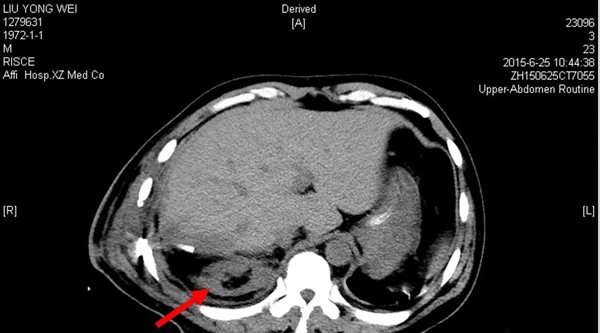

3、術(shù)后分別于2015年6月21日(術(shù)后第1天)和6月25日(術(shù)后第5天)的2次CT復(fù)查均顯示該患者的右腎存在。(圖一、圖二)

圖二 2015年6月25日(術(shù)后第5天)CT,右腎如箭頭所示。